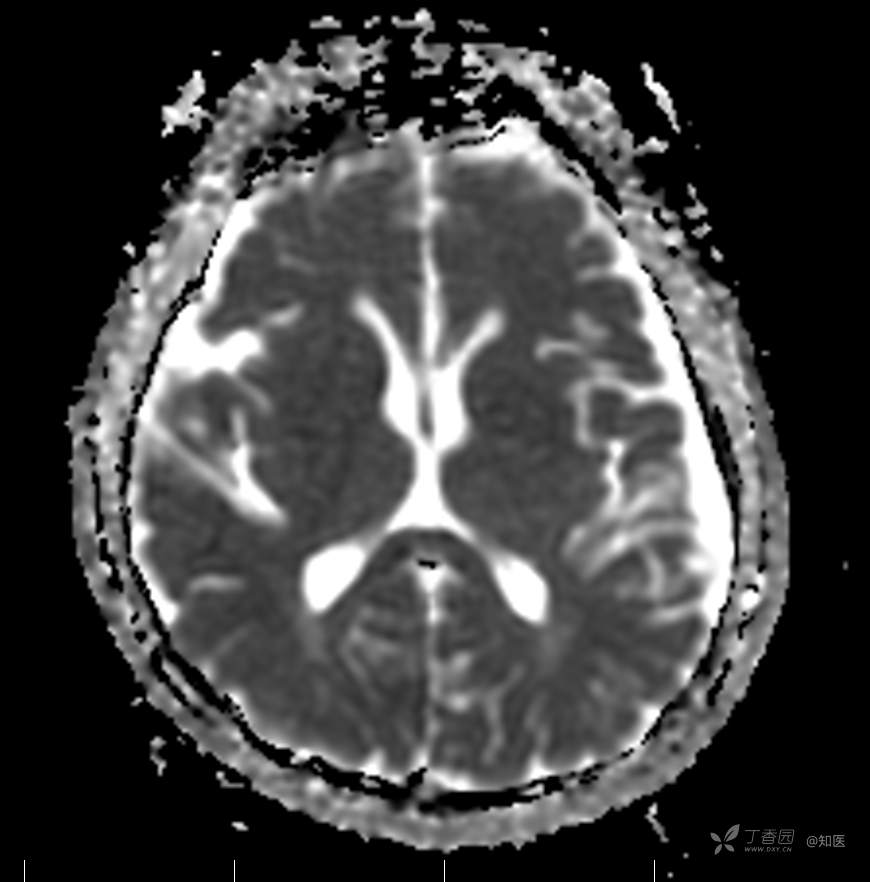

2021-6-15 ADC

2021-06-16日晨查房,患者自觉入院治疗后肢体无力症状较前稍改善,仍有活动后气短,余未诉特殊不适。ALSFRS-R评分:44分(单项均大于等于2分)。血压:123/63mmHg。神经系统查体:GCS 15分,右利手,查体合作,问答切题,粗测智能基本正常。额纹对称,双眼闭目紧,双侧瞳孔等大等圆,直径约3.0mm,对光反射灵敏,眼球运动自如,无眼震,双侧鼻唇沟对称等深,口角无歪斜。悬雍垂居中,双侧软腭抬举良好,咽反射灵敏、转颈、耸肩均一致有力。颈屈肌、颈伸肌力量5级。伸舌居中,无舌肌纤颤及萎缩。双侧岗上肌、岗下肌可见萎缩;双侧三角肌可见偶发肉跳、肌力5级,左侧肱二头肌肌力4+级、右侧4-级,双侧肱三头肌肌力4+级;双手握力可,双手大小鱼际肌及第一骨间肌可见萎缩,左侧明显,左侧手腕背伸力量4级、右侧4+级,双侧拇短展肌肌力4-级,双侧示指伸肌肌力3级,左侧指总伸肌肌力4级、右侧4-级,双侧小指展肌肌力4-级。双上肢肌张力对称减低。左侧肱二头肌反射迟钝、右侧未引出,双侧桡骨膜反射及肱三头肌反射未引出。左侧胸大肌反射阳性、右侧未引出,双侧Rossolimo征阳性、Hoffmann征阴性,下颌反射阴性。腹壁反射未引出。双下肢可见肌肉萎缩,以左侧明显;左侧髂腰肌肌力4级、右侧4-级,双侧股四头肌肌力5级,双足背伸力量3级,左足跖屈力量4级、右足4+级。双下肢肌张力对称基本正常。双侧膝腱反射、跟腱反射迟钝,双侧跖反射消失,双侧巴氏征未引出。右侧大腿外侧肌肉活检瘢痕周围浅感觉缺失,余肢体及躯干深浅感觉正常,共济运动对称正常。颈软,无抵抗,双侧布氏征及克氏征均阴性。辅助检查:微量元素(钙、镁、铁、铜、锌),微量元素测定(铅,镉)[复][2021-6-16 16:11:07]:钙1.19mmol/l;铁9.00mmol/L。急诊电解质七项[复][2021-6-16 10:41:41]:钾3.55mmol/L。血细胞分析+五分类[2021-6-16 9:57:17]:淋巴细胞百分比19.5%。[头颅,扩散成像(DWI)][头颅,磁敏感成像(SWI)][头颅,水抑制成像(FLAIR)][2021-6-16 18:10:50]:1.多发腔梗,脑白质脱髓鞘,脑萎缩。2.DWI:脑实质内未见明显高信号。3.磁敏感成像脑实质内未见明显异常信号灶。MMSE:26分(高中文化水平)。MoCA:23分。ADL评分:14分。ECAS评分:96分(ALS特异67分、ALS非特异29分)。肌电图:提示颈髓、腰髓、胸髓和延髓支配肌肉可见活动期神经源性损害,颈髓和腰髓支配肌肉同时可见慢性期神经源性损害;提示脊髓前角细胞损害可能,请结合临床。心电图大致正常。外送基因检查:TBK1基因杂合子,提示额颞叶痴呆和(或)肌萎缩性侧索硬化症4型。二线主治医师查看患者后示:1.患者基因检查结果显示TBK1基因杂合子,提示额颞叶痴呆和(或)肌萎缩侧索硬化症4型,结合外院影像学检查可见额颞叶萎缩明显,来院后复查头颅FLAIR+DWI+SWI亦提示脑萎缩,量表评估提示认知功能稍减退,ECAS评分基本正常。综上,修正诊断:肌萎缩侧索硬化症(ALS) 额颞叶变性 低钾血症 高血压2级(高危) 多发腔隙性脑梗死。因TBK1基因引起的额颞叶痴呆和(或)肌萎缩侧索硬化症为常染色体显性遗传,患者父亲已逝,母亲健在,诉无明显认知功能障碍或肌肉萎缩等表现,建议患者母亲抽血送检,进一步明确致病基因来源,必要时患者子女也可行基因检查进一步明确。2.患者目前诊断基本明确,根据文献报道,合并FTD的ALS患者整体生存周期较短(约19个月),目前患者发病已1年余,应充分与患者家属沟通病情,告知疾病预后及生存周期情况,同时建议开始口服利鲁唑片,延缓疾病进展。余治疗方案暂不予调整。密观病情变化,遵嘱执行。

2021-06-18出院总结: 卫某某,男,60岁,以“四肢僵硬1年,加重伴无力半年”之主诉入院。查体:生命体征平稳,心肺腹查体无明显异常。神经系统查体:GCS 15分,右利手,查体合作,问答切题,粗测智能基本正常。额纹对称,双眼闭目紧,双侧瞳孔等大等圆,直径约3.0mm,对光反射灵敏,眼球运动自如,无眼震,双侧鼻唇沟对称等深,口角无歪斜。悬雍垂居中,双侧软腭抬举良好,咽反射灵敏、转颈、耸肩均一致有力。颈屈肌、颈伸肌力量5级。伸舌居中,无舌肌纤颤及萎缩。左侧肱二头肌肌力4+级、右侧肱二头肌及双侧三角肌肱三头肌肌力5级;左手大小鱼际肌可见萎缩,左手握2指松、右手握力可,左手拇短展肌、示指伸肌、指总伸肌及抬腕力量3级,右手拇短展肌、示指伸肌、指总伸肌及抬腕力量4-级。双上肢肱二头肌反射、肱三头肌反射、桡骨膜反射均对称减低;双侧Hoffmann征、Rossolimo征、胸大肌反射及掌颏反射阴性,下颌反射阴性。双侧上、中、下腹壁反射可引出。左侧髂腰肌肌力4-级、右侧髂腰肌肌力4级,双侧股四头肌肌力5-级;右足背伸力量3级、左足背伸力量2级,双足跖屈力量5级。双下肢膝腱反射、跟腱反射对称减低;双侧膝阵挛、踝阵挛未引出。双侧巴氏征、Chaddock征均未引出。右侧大腿外侧肌肉活检处周围浅感觉减退,余四肢及躯干部深浅感觉正常,共济运动对称正常。颈软,无抵抗,双侧布氏征及克氏征均阴性。辅助检查:肌电图(2021-05-08,某军医大学附属医院):神经源性损害(颈段、腰骶段受累,胸段可疑;重复神经电刺激(低频、高频)可见左腋神经递减现象。 肌肉活检(2021-05-18,某军医大学附属医院):(右股四头肌)考虑神经源性损害,建议结合临床除外运动神经元病等。入院诊断:1.肢体无力:肌萎缩侧索硬化症(ALS);2.高血压1级(中危)。入院后查血清蛋白电泳:α2-球蛋白6.50%。凝血六项:血浆凝血酶原时间比值0.93;凝血酶原国际标准化比值0.93。贫血因子三项:维生素B12>1476.00pmol/L。平诊肝功十三项+平诊心肌酶谱五项+血同型半胱氨酸测定+平诊血脂八项+平诊肾功七项+平诊电解质八项:尿素3.05mmol/L;肌酐49umol/L;钾3.15mmol/L;高密度脂蛋白0.99mmol/L;载脂蛋白A1.131g/L;脂蛋白(a)333mg/L;肌酸激酶420U/L;总胆红素22.1umol/L;直接胆红素5.4umol/L。微量元素(钙、镁、铁、铜、锌),微量元素测定(铅,镉):钙1.19mmol/l;铁9.00mmol/L。急诊电解质七项:钾3.55mmol/L。血细胞分析+五分类:淋巴细胞百分比19.5%。[头颅,扩散成像(DWI)][头颅,磁敏感成像(SWI)][头颅,水抑制成像(FLAIR)]:1.多发腔梗,脑白质脱髓鞘,脑萎缩。2.DWI:脑实质内未见明显高信号。3.磁敏感成像脑实质内未见明显异常信号灶。MMSE:26分(高中文化水平)。MoCA:23分。ADL评分:14分。肌电图:提示颈髓、腰髓、胸髓和延髓支配肌肉可见活动期神经源性损害,颈髓和腰髓支配肌肉同时可见慢性期神经源性损害;提示脊髓前角细胞损害可能。血尿粪常规、免疫八项、风湿三项、血沉、传染指标、血同型半胱氨酸、糖化血红蛋白等未见明显异常。心电图、肺通气功能大致正常。住院期间给予营养神经、清除氧自由基等对症支持治疗。现患者诊断基本明确,生命体征平稳,一般情况良好,可予今日出院。出院诊断:1.肌萎缩侧索硬化症(ALS);2.额颞叶变性;3.低钾血症;4.高血压2级(高危);5.多发腔隙性脑梗死。出院医嘱:1.注意休息,加强营养,低盐、高蛋白高纤维素饮食,注意休息,适当锻炼,避免剧烈运动及重体力劳动。2.出院继续口服药物:甲钴胺 500ug/次,3次/日;辅酶Q10 10mg/次,3次/日;维生素E 100mg/次,2次/日;美金刚 10mg/次,1次/日;利鲁唑片,50mg/次,2次/日,与餐间隔1.5-2小时。3.出院继续用依达拉奉(必存)60mg+0.9%氯化钠 200ml,静滴,1次/日(首疗程14天,后每疗程10天,间隔20天,共使用6个疗程)。4.1月后门诊复查血常规、肝肾功能、电解质功能;3月后我科门诊再次复诊。5.不适随诊。